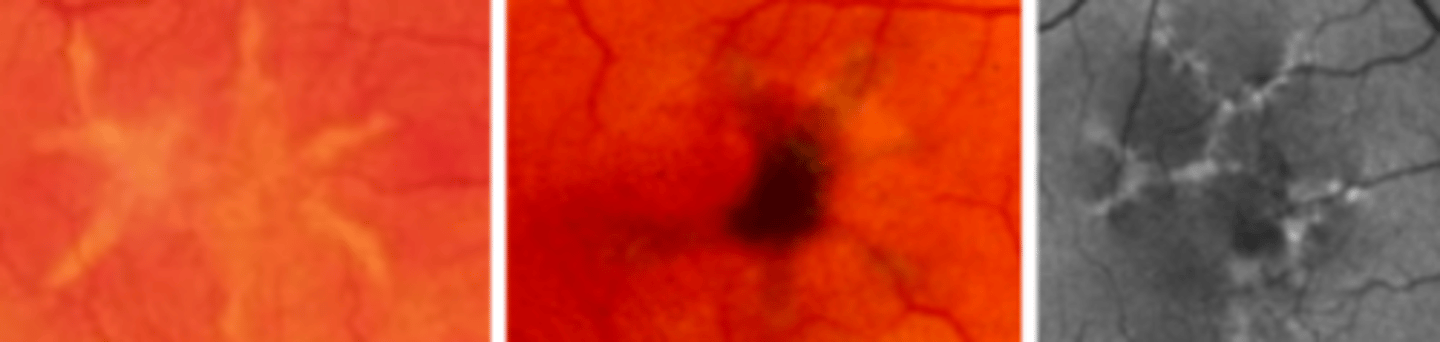

Retinitis Pigmentosa (pigmentary retinal dystrophy)

ROD cone dystrophy condition characterized by genetic defects in the production of photoreceptor proteins resulting in bilateral melanin pigment clumping and subsequent early degeneration of rods and of cones in later stages due to a defect in the rhodopsin gene. Presents as loss of peripheral vision with the first symptom usually being loss of night vision. Genetic counseling and referral to low vision indicated. Long term prognosis is poor.

Arteriolar attenuation, retinal bone spicule pigmentation, waxy disc pallor

classic triad of retinitis pigmentosa

Cataracts, myopia, CNVM

three common ocular associations with retinitis pigmentosa

Posterior subcapsular cataract

cataract that is associated with retinitis pigmentosa and can be very debilitating in a patient already having peripheral vision loss

scotopic ERG, pattern ERG, photopic ERG and EOG

Retinitis pigmentosa will show early ____ reduction with normal ____. In later stages _____ will be reduced or absent

Usher syndrome, Freidreich ataxia

two systemic syndromes associated with retinitis pigmentosa